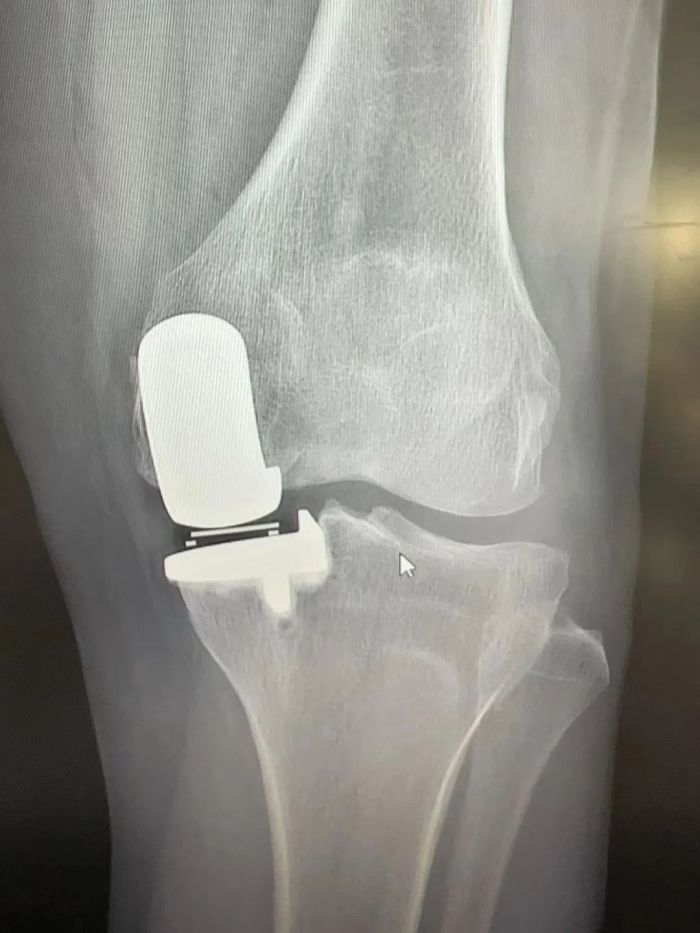

手术由吴韧教授指导、骨科一病区(关节、脊柱)行政主任易平主刀,术中医疗团队凭借精湛的技术和丰富的经验,精准地完成了每一个步骤。手术时间短,出血量少,术后患者状态良好。

术后患者膝关节情况